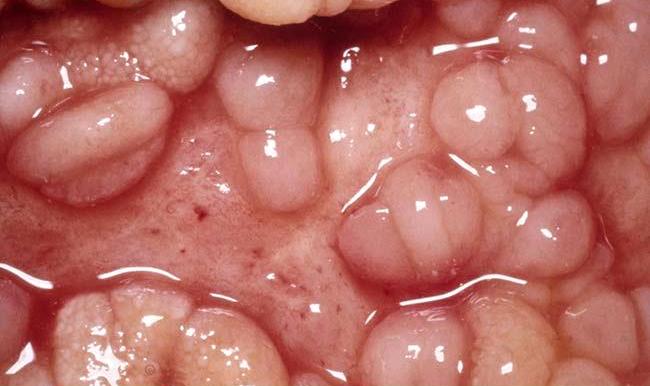

Νόσος του Crohn

Η νόσος του Crohn είναι μια φλεγμονώδης νόσος και επώδυνη για τους ασθενείς κατάσταση που μπορεί να προσβάλει οποιοδήποτε τμήμα του πεπτικού συστήματος. Συνήθως όμως προσβάλει το τελικό τμήμα του λεπτού εντέρου (ειλεός) και το αρχικό του παχέος εντέρου.

• Κολονοσκόπηση: Η συχνότερη εξέταση για τη διάγνωση της νόσου του Crohn, δίνει μια πολύ ακριβή εικόνα της εσωτερικής επιφάνειας του εντέρου και επιτρέπει στον γιατρό να λάβει δείγματα για εξέταση σε εργαστήριο εφόσον χρειαστεί. Εάν το παχύ έντερο και το τελικό τμήμα του λεπτού εντέρου εμφανίζονται φυσιολογικά, τότε είναι εξαιρετικά απίθανο να υπάρχει νόσος του Crohn.